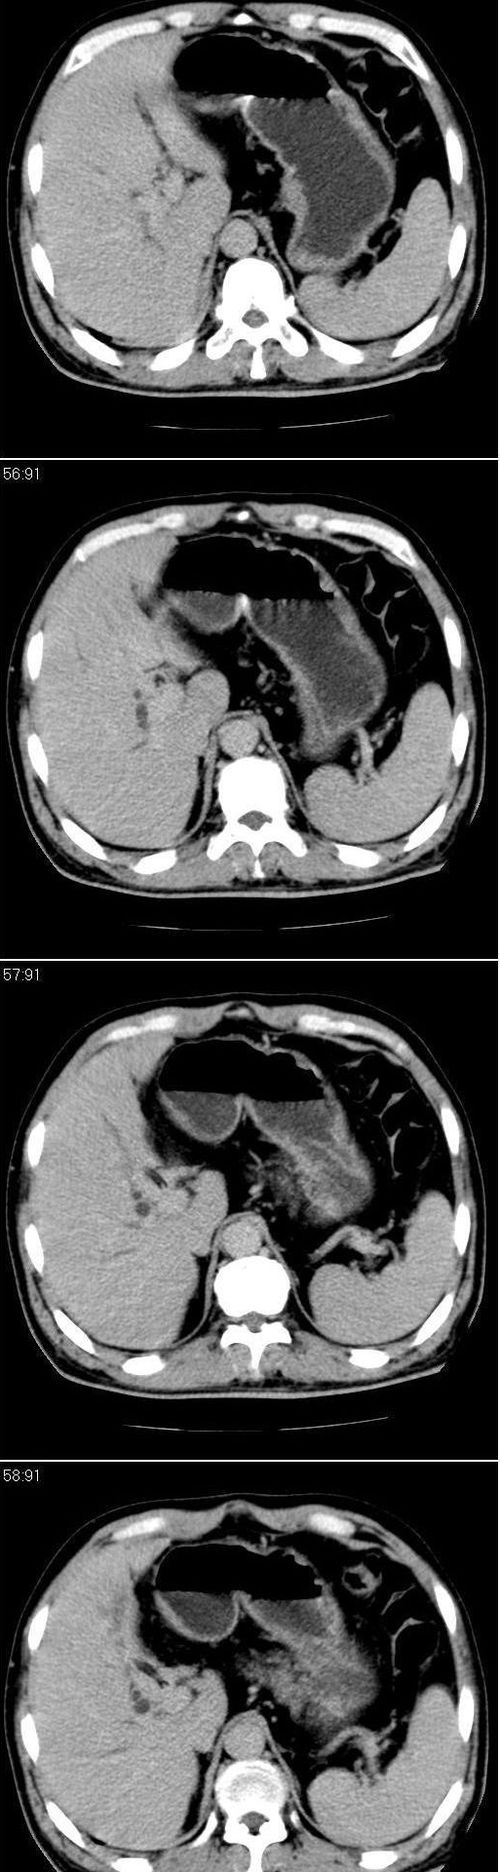

标题: CT13147:男,57岁。因胆结石阻塞性黄疸入院。 [打印本页]

标题: CT13147:男,57岁。因胆结石阻塞性黄疸入院。

男,57岁。因胆结石阻塞性黄疸入院。这是胆囊切除术后的照片,看看此片到底有什么问题。

胆总管有没有问题,尤其是肝门附近的胆总管?

肝门附近的胆总管轻度扩张 请楼主复习术前片

在手术切除胆囊的过程中,发现肝门部胆总管恶性占位,因为家属不同意手术,没有切除,能看出来么?

不是楼主提醒还真看不出来,肝内胆管扩张。略显僵硬。

肝内外胆管轻度扩张。楼主提示左右肝管合汇区域壁稍厚。胆总管末段壁似也稍厚有轻度强化。就现有资料诊断难。